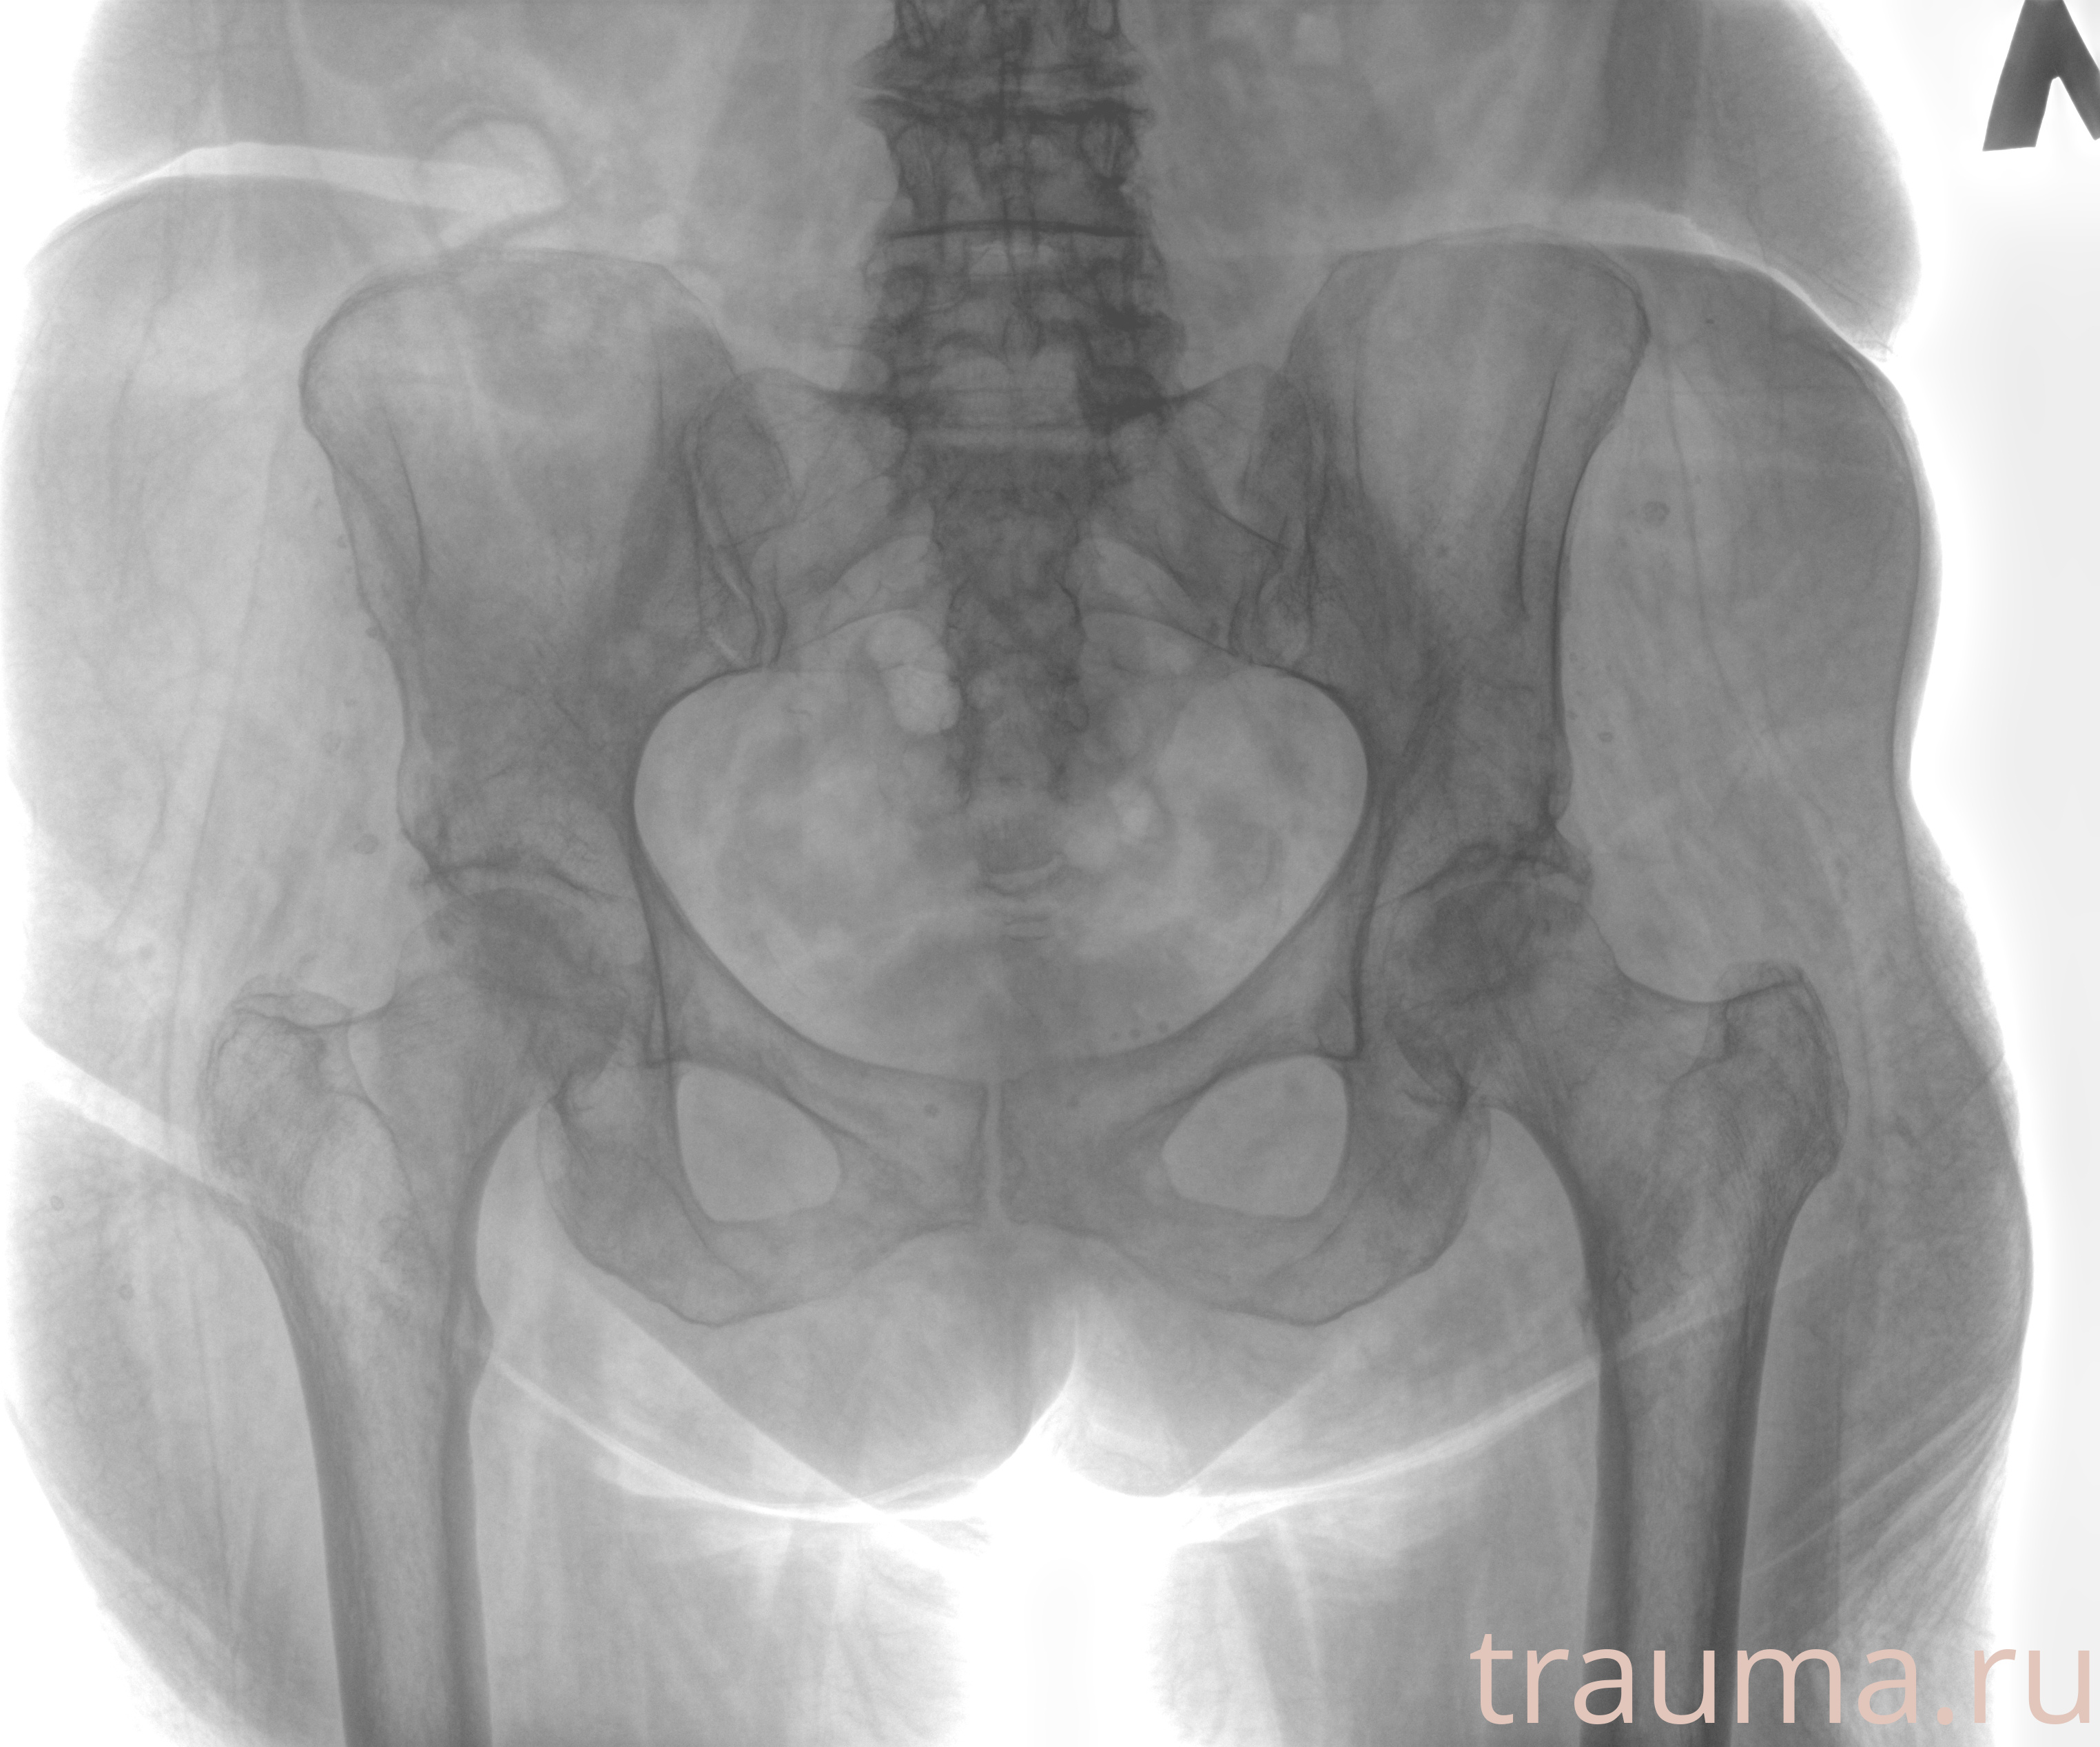

Рентгенограммы

Рентген на дому: по вашему адресу приезжает врач-рентгенолог, травматолог-ортопед с мобильным рентгеновским аппаратом, проводит диагностику травмы или заболевания, делает необходимые рентгенограммы, дает рекомендации по дальнейшему лечению. Получить качественные снимки в домашних условиях возможно благодаря уникальной методике, разработанной МосРентген Центром для института  Склифосовского